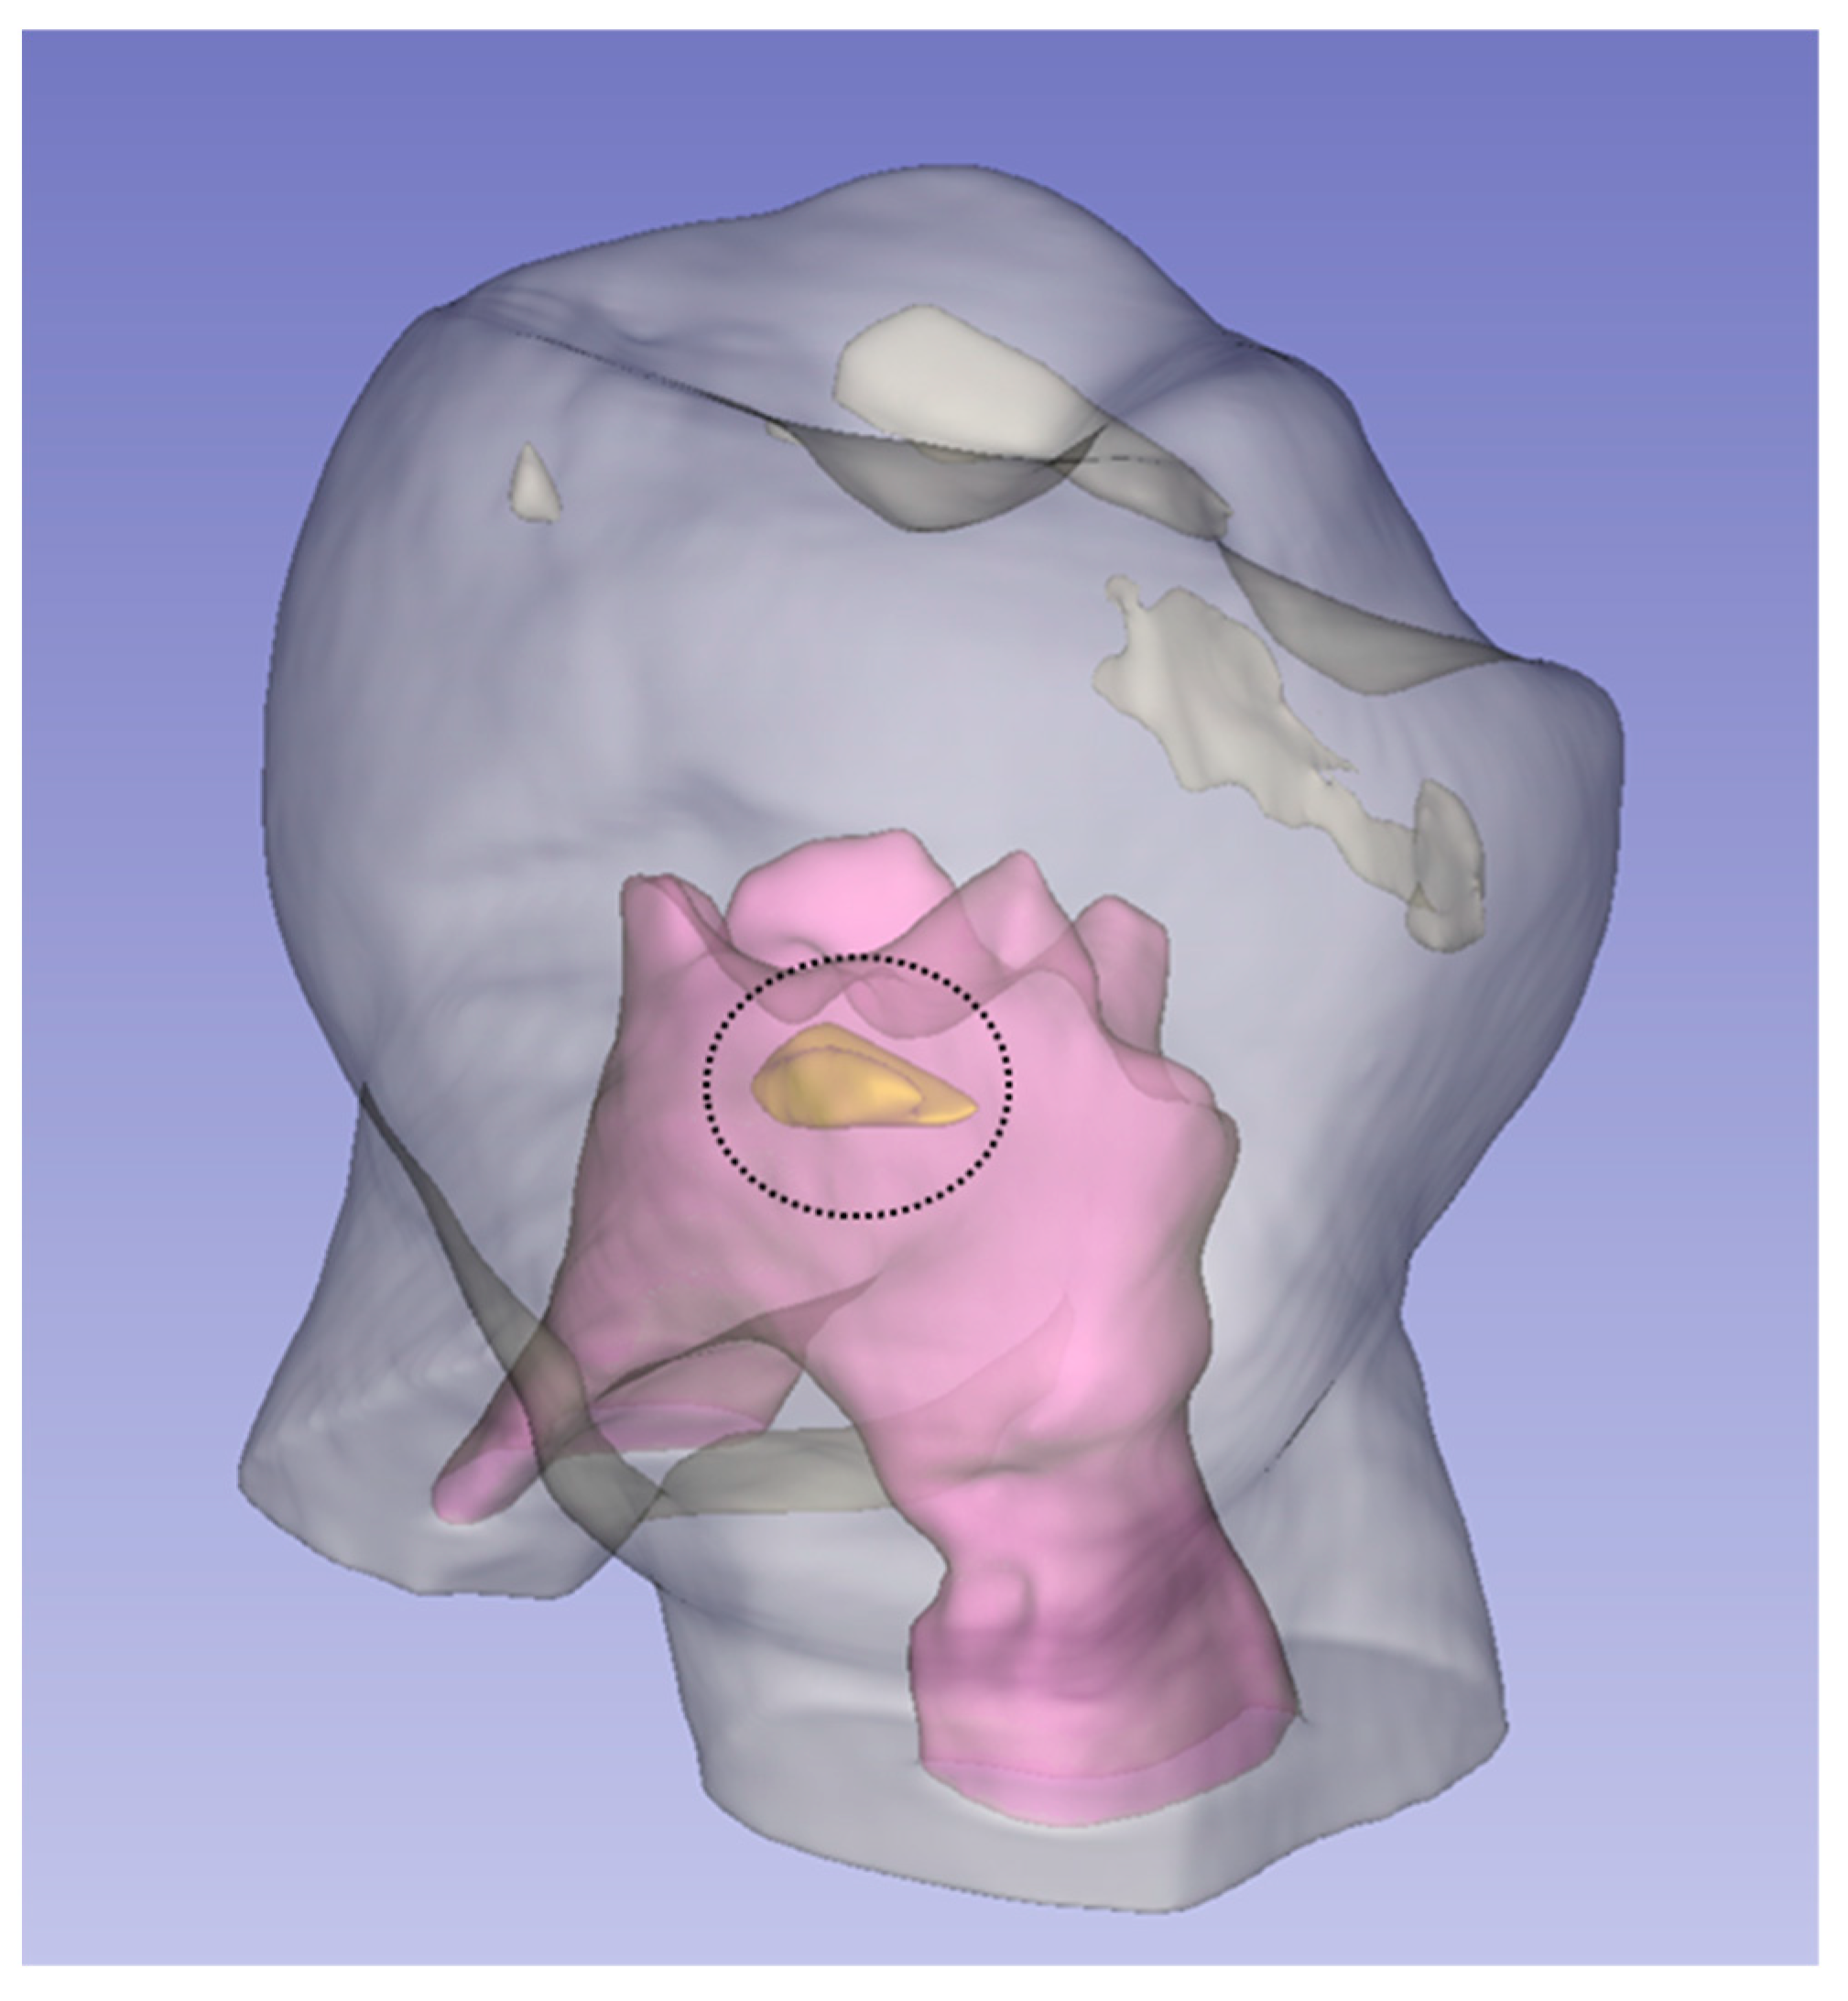

2.4. Measurements

2.4.1. Pulp Chamber Roof (PCR) and Pulp Chamber Floor (PCF)

2.4.2. Distance between Pulp Chamber Floor and Furcation (FD)

2.4.3. Pulp Chamber Volume (PV), Dental Crown Volume (CV), and Volume Ratio (VR)

2.4.4. Other Peculiarities